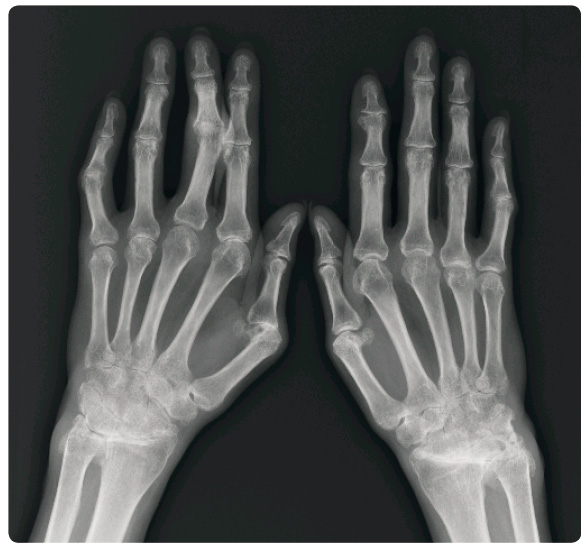

Proto byla navržena změna léčby a v listopadu 2013 bylo zahájeno podávání golimumabu, kterým je pacientka úspěšně léčena až dodnes. Subjektivní obtíže spojené s injekcí se sice od počátku léčby vyskytovaly v malé míře dále, nicméně se snesitelnou frekvencí jednou měsíčně. Pacientka je dlouhodobě bez kloubních obtíží, s léčbou je spokojena a dosažený terapeutický úspěch měl vliv i na její úzkostné vnímání nežádoucích účinků, které se během léčby podstatně zmírnilo. Po dvou letech léčby je pacientka v remisi, má normální hodnoty reaktantů zánětu a stabilizovaný je rovněž rtg nález (obr. 1).

ústavu. Při prvním vyšetření byla zjištěna pokročilá polyartikulární forma PsA. Pacientka měla bolestivé a oteklé zejména klouby rukou (zápěstí oboustranně, na pravé ruce metakarpofalangeální, MCP, skloubení II–V, PIP V vpravo, PIP III vlevo), současně byly již patrny deformity – semiankylózy obou zápěstí, mírná ulnární deviace v MCP skloubeních pravé ruky, deformity „stříšky“ na pátém prstu pravé ruky a na čtvrtém a pátém prstu levé ruky. Klouby dolních končetin postiženy nebyly. Pacientka měla vysokou hodnotu FW (81/h) a mírně zvýšenou hodnotu CRP (13,82 mg/l). Na rtg snímku byly patrné rozsáhlé destruktivní změny v oblasti rukou a nespecifické změny nevylučující postižení páteře (obr. 2).